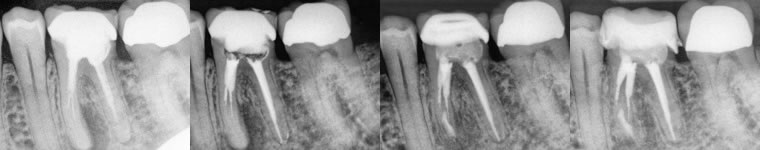

2. Very well done original endodontic therapies.

These would often be scenarios to which we know the specific history of the original root canal treatment, such as treatment that we had originally provided. (figures 4,5) (figures 6,7,8)

Figures 4-5: pre-op / immediate post-op

Original RCT’s performed by myself, but lesions never healed after 2 years and thus apicoectomy performed just a couple months ago. I do not have a long enough recall at this point, but the buccal fistula has fully healed.

Figures 6,7,8: pre-op / post-op / 14 month recall

Original RCT performed by myself and a lesion developed 2 years later. I of course knew this case well and that the tooth was treated in a multi-visit approach using calcium hydroxide. I felt apicoectomy would be a more definitive approach and the healing has been excellent.